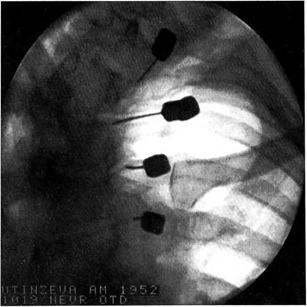

Манипуляция выполнялась в операционной в амбулаторных условиях. В положении больного на животе под местной анестезией (10 мл 2% раствора лидокаина) под контролем электронно-оптического преобразователя производили пункцию параартикулярной области в зоне расположения нервов, идущих к суставной капсуле. Как правило, одномоментно выполняли пункцию на трех—четырех уровнях с одной стороны. В 2 случаях в связи с тяжестью заболевания пункция проводилась с обеих сторон. Положение иглы контролировали в двух проекциях. Затем с помощью радиочастотного генератора RFG-3C PLUS фирмы «Radionics» осуществляли электростимуляцию фасеточных нервов с частотой 50 и 2 Гц. Наличие болевой реакции считали критерием корректного положения иглы (рис. 3).

Рис. 3. Радиочастотная деструкция фасеточных нервов в поясничном отделе позвоночника.